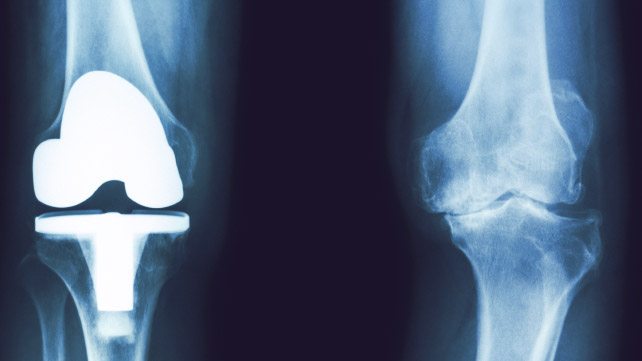

- выяснение необходимости и возможности эндопротезирования;

- контроль состояния суставных и околосуставных тканей после установки имплантата;